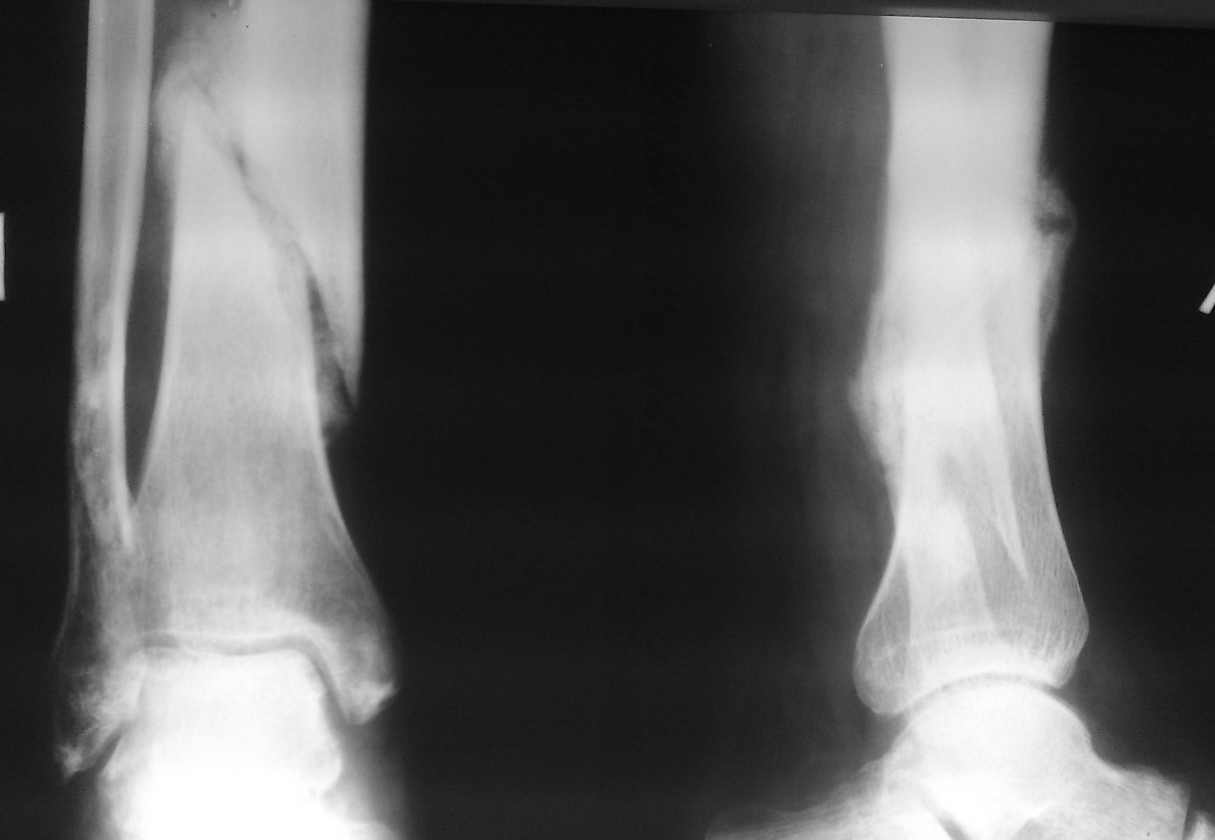

Насчет косметичности именно внешней фиксации в сравнении с малоинвазивной внутренней - вот примерчик. Первое фото после снятия аппарата перед штифтованием, а воторая картинка через год после штифтования. Поглядите, от чего осталось больше следов.

пример функционального лечения по Сармиенто похожего перелома. Рентгенограммы в 1 мес, 3,5 мес, фото и видео 3,5 мес. Движения в колене в полном объеме, в голеностопе - небольшое ограничение (пара дней после снятия повязки), нагрузка безболезненная.

почему-то не приложились снимки, продублирую